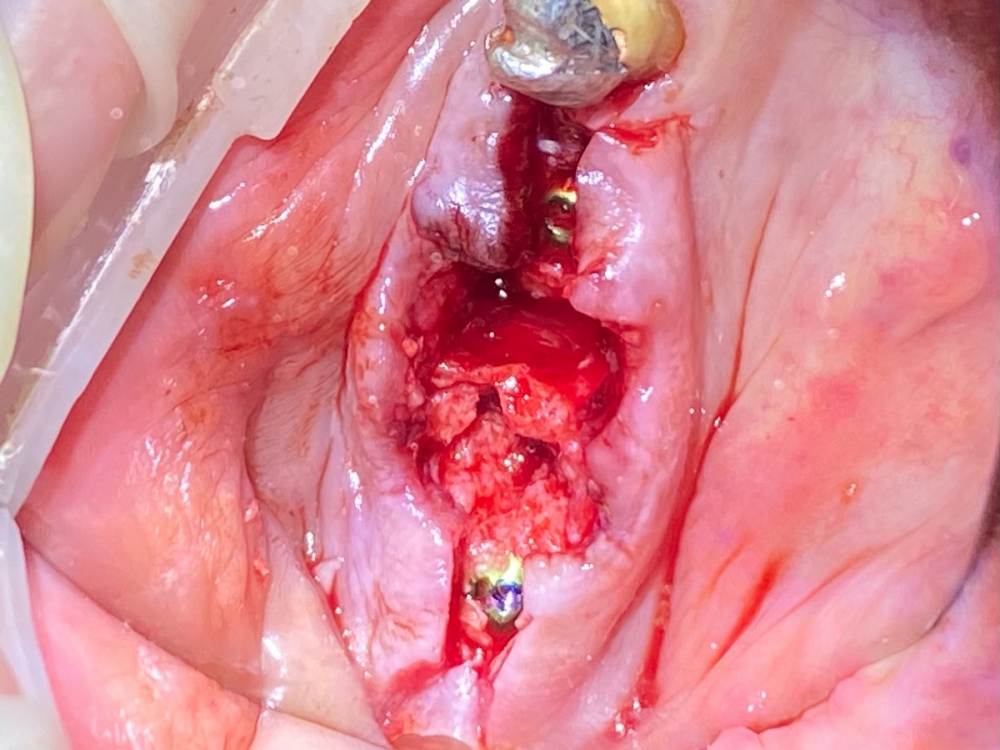

А вот снизу вариантов кроме одностороннего съёмника или имплантации не было. Поэтому план: удалить 4.6, выскрести всю гадость, имплантация 4.5-4.7 и мостовидная конструкция в будущем, также планировал работу с десной, но скелетировав кость понял, что биотип толстенный и нет в этом смысла.

Кость D1. Очень старался не перегреть.

Пациент бросающий курильщик (хорошо хоть не барабанщик), поэтому заглушка, швы. Хотя торк около 50, имплантиумы, 4.5 на 10 и 8 соответственно.

Коллеги, во время пилотного сверления как в области 4.5 так и в области 4.7 пациент отметил резкую боль. Если покрутить КТ, то как раз в местах планируемых имплантатов есть небольшие костные дефекты (хотя конечно на дефект это не тянет, тогда как называть?).

Также, само-собой, во время шкрябинга после удаления 4.6 грануляции были болезненны. И тут я могу понять, но когда зубы удалены около 3 лет назад? Объясните почему так, если кто-то знает пожалуйста.

Немного аутокости со сверла уложил в области 4.7.